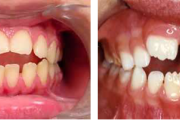

Vali sind huvitav pilt ja me näitame sellega seotud haigust ja sümptomeid